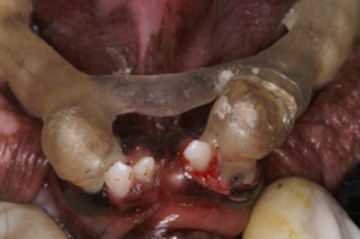

La persistencia de los caninos deciduos provocan interferencias oclusales severas por la erupción ectópica de los caninos permanentes que al no tener una guía adecuada de erupción, tienden a colocarse mesialmente a su posición normal. Esta situación provoca que en vez de que la superficie mesial de los caninos superiores permanentes contacte con la superficie distal de los caninos inferiores, sea la punta incisiva de los caninos superiores la que contacta con la superficie distal de los caninos inferiores provocando un adelantamiento de la mandíbula presentándose una pseudo oclusión clase III, o sea un pseudo prognatismo con mordida cruzada anterior. Por eso, es importante antes de que erupcionen los caninos permanentes saber cuando es el periodo de exfoliación de los caninos temporales para en caso de ser necesario extraerlos y evitar esta grave maloclusión. Otra situación no tan común es cuando existen dientes supernumerarios que provocan apiñamiento. En estos casos se extraen los dientes supernumerarios antes de que se presente el apiñamiento severo y de esta manera evitamos la maloclusión.

Evitar la pérdida de dientes por enfermedad periodontal, caries, fracturas, desgaste excesivo, etc. es importantísimo ya que los espacios que quedan provocan el movimiento de los dientes contiguos y la sobre erupción de los dientes antagonistas. Como vemos, la ortodoncia preventiva juega un papel importantísimo en la prevención de la maloclusión por lo que es muy importante tener una tabla de erupción dental en las diferentes razas de perros ya que existen variaciones en el tiempo dependiendo principalmente del tamaño y conformación del paciente.